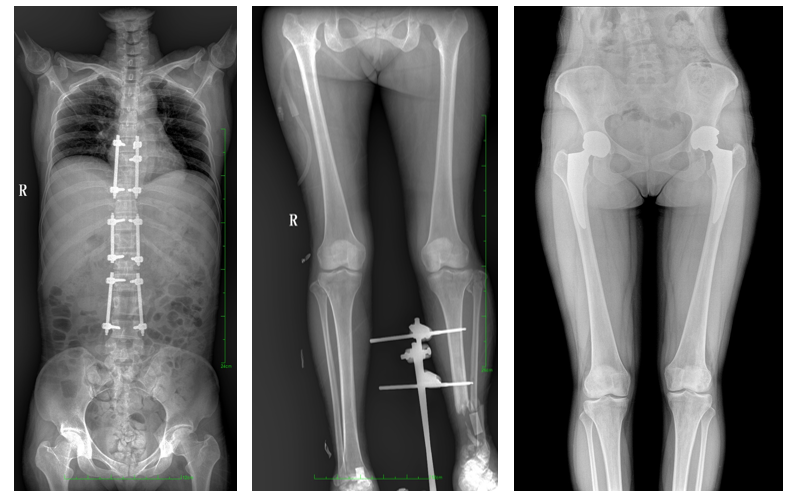

17"*34"有效視野,是市面大尺寸平板的2倍,一次成像不拼接。相較于多張攝影再軟件拼接的DR設(shè)備,PLX8600解決了拼接圖像存在密度不均勻,拼接處圖像配準(zhǔn)和放大效應(yīng)等問(wèn)題,給臨床帶來(lái)了真正的大視野影像解決方案,高清畫質(zhì),準(zhǔn)確成像不失真,可一次性覆蓋全脊柱或雙下肢影像。PLX8600大視野平板動(dòng)態(tài)DR攝影速度快,患者可以更快的完成檢查,且單次攝影輻射劑量是常規(guī)多張攝影再軟件拼接DR的1/2或1/3,低劑量給患者更多關(guān)愛(ài)。

除常規(guī)靜態(tài)攝影外,PLX8600大平板具備動(dòng)態(tài)透視和點(diǎn)片功能,透視采集功能可支持大視野、多角度的可視化觀察。通過(guò)可視化的動(dòng)態(tài)影像,配合點(diǎn)片功能,能夠很好的觀察復(fù)雜部位病灶,有效的抓取關(guān)鍵幀,降低患者多次攝片的概率,安全又高效。如:全脊柱狀態(tài)評(píng)估、長(zhǎng)骨關(guān)節(jié)活動(dòng)度、下肢靜脈造影瓣膜功能評(píng)估、消化道功能評(píng)估、脊髓造影等更多大視野臨床應(yīng)用,多面手給醫(yī)生更多驚喜。